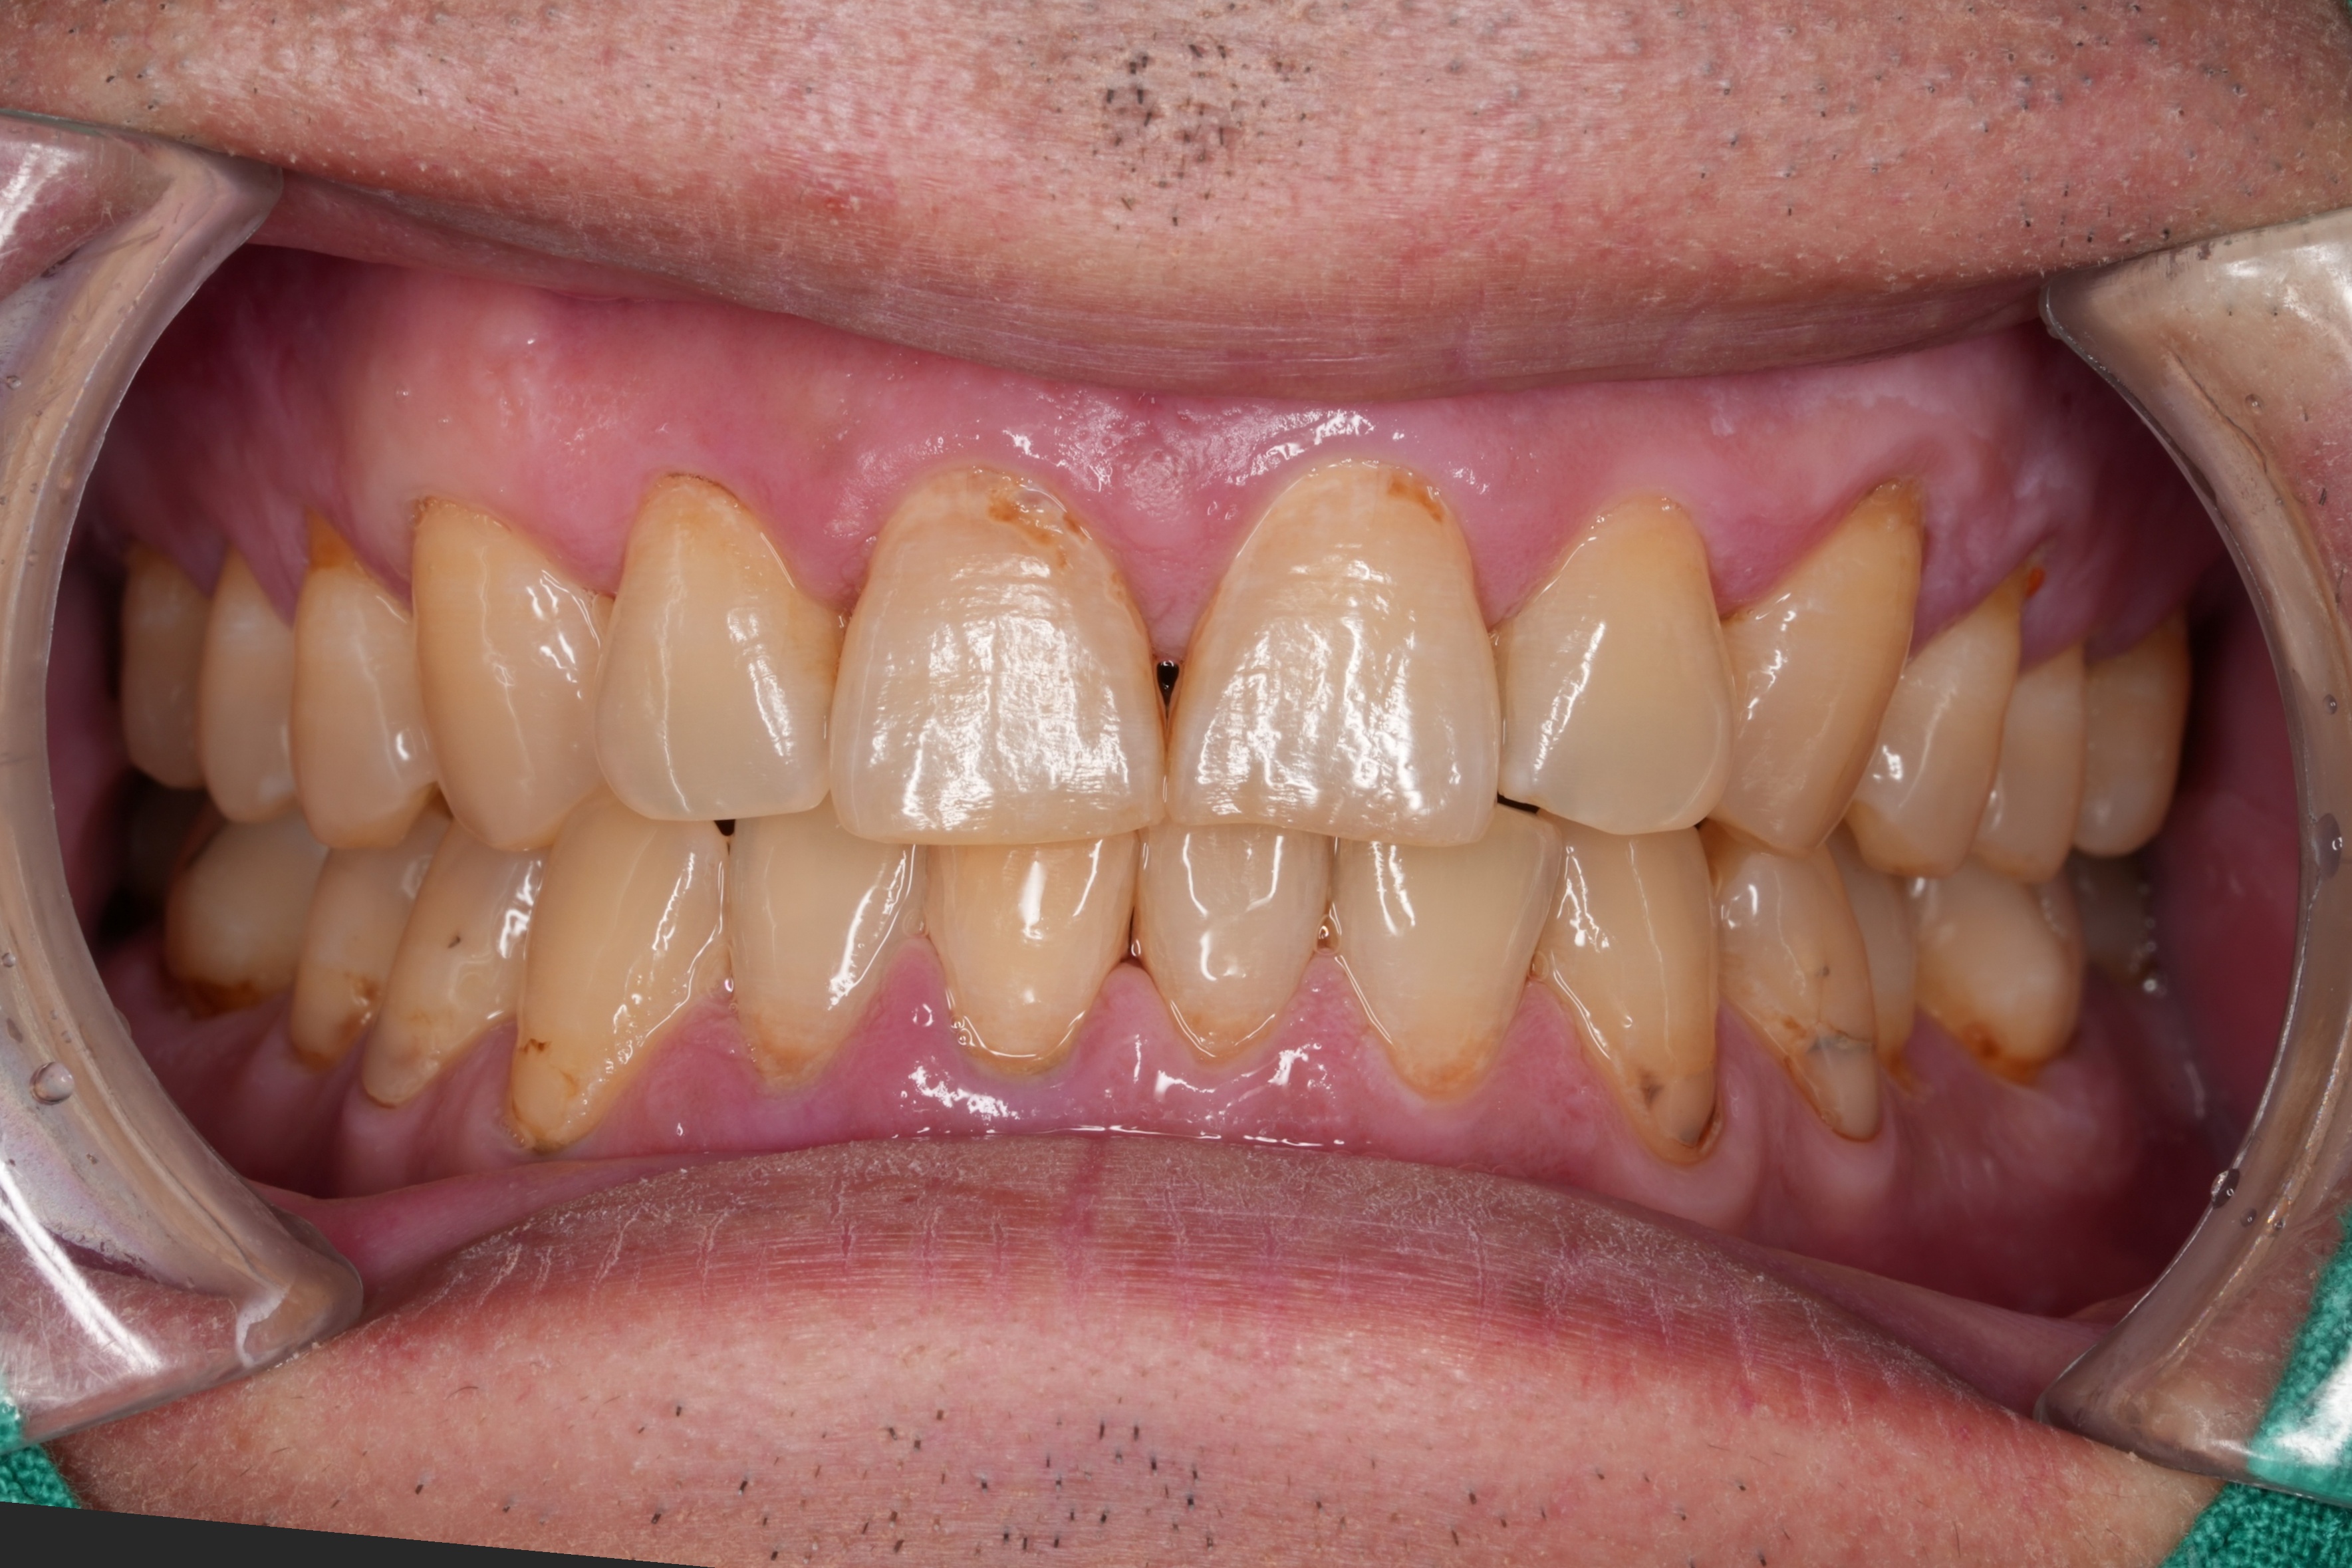

BEFORE상악 전치부 치경부 충치치료 구강 비포

앞니 잇몸 경계 부위(서비컬)에 생긴 충치를, 치아 색과 자연스럽게 어울리는 레진으로 채워 치료했습니다. 충치 부위만 최소한으로 삭제하고, 치아 본래의 형태를 살려 마무리했습니다.